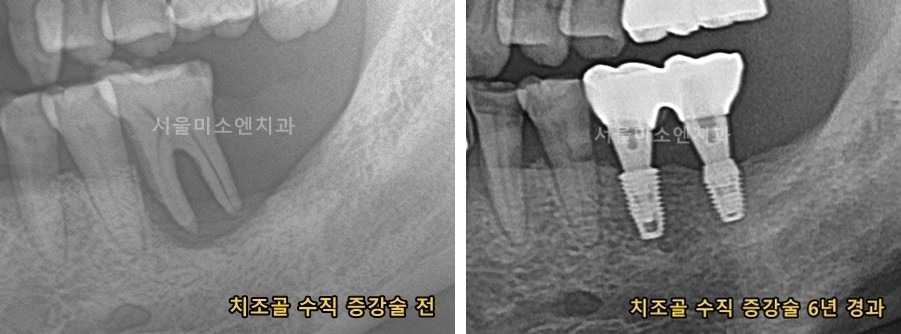

치조골 이식 수술이 필요한 경우를 제가 경험한 예를 들어서 말씀드리겠습니다. 저 같은 경우는 신경 치료 후 크라운을 씌웠습니다. 그런데 치아 잇몸에 염증이 생겨 해당 이의 뼈가 녹아내렸습니다. 결국 해당 치아는 발치를 하였습니다.

이런 경우가 임플란트를 위한 치조골 이식수술이 필요합니다. 그럼 이런 경우 임플란트 비용은 어떨까요?